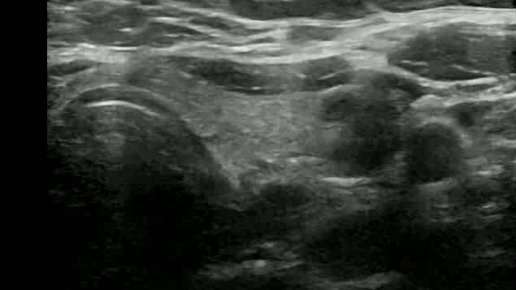

Видео к статье "Стратификация узлов щитовидной железы. TI-RADS-5" https://dzen.ru/a/ZwTJQTbM3zpM5Y6F

Ультразвуковые находки от врача УЗД Зорина Я.П.